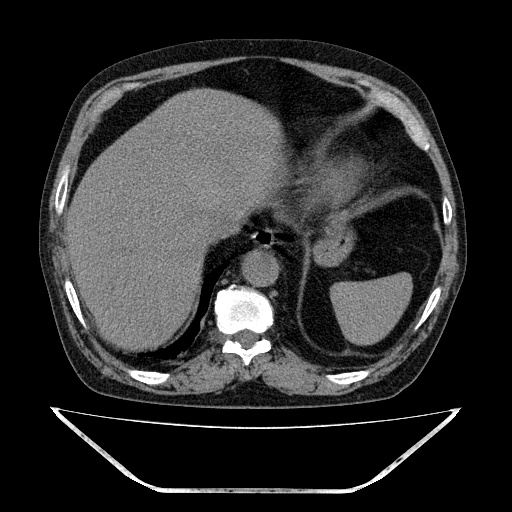

双肺多发结节影,以肺周围分布较多,纵隔淋巴结肿大,考虑双肺转移瘤可能性大。

另胸椎旁改变考虑神经鞘瘤可能性大

1双肺转移性肺癌,2t12~l1右侧椎旁神经鞘瘤。

双肺多发转移瘤。纵隔淋巴结肿大。胸椎右旁软组织结节,考虑神经源性肿瘤,请进一步检查。

胸椎旁软组织密度影,与椎管内结构相连,相应椎间孔开大,考虑为神经源性肿瘤(神经鞘瘤)可能

1双肺及纵隔淋巴转移性病变,2t12~l1右侧椎旁神经鞘瘤。

双肺多发转移瘤,纵隔淋巴结肿大。胸椎右旁软组织结节,考虑神经源性肿瘤,请进mri。

支持 1、双肺转移瘤伴纵隔淋巴结肿大 2、右侧椎旁神经鞘瘤可能性大

胸椎右旁软组织结节,考虑神经源性肿瘤。